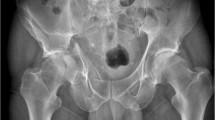

Traditional acetabular fractures were taught through didactic lectures with 2D images (both XR and CT scan) or various algorithms and flowcharts for acetabular fracture classification [7]. However, these methods are non-intuitive and often difficult to translate into a 3D interpretation of the fracture pattern [8]. In addition, the fracture classification and textbook descriptions are generalised into the key main characteristics or patterns, however fracture lines seldom follow the classic patterns in real-life clinical scenario (Fig. 1). Besides the complexity of these fractures, its low incidence coupled with regulation of training hours result in learning opportunities becoming far and few [9, 10]. This has necessitated alternative education tools like computer-based simulator modules and other skills training models, employed in different medical speciality curriculum with varying degree of success [11].

Participants in Group 1 were the control group who received only traditional didactic lecture via power-point slides including the basics of acetabular fracture anatomy, classification scheme and algorithms, surgical approaches and treatment using relevant diagrams and radiological imaging. The participants in Group 2 were given the 3D printed models of acetabular fractures during the teaching lecture to physically handle the pelvic models and appreciate each fracture pattern. Judet and Letournel classified acetabular fractures in 5 elementary and 5 associated fracture types [31]. All the fractures were taught to residents during the lecture using pertinent radiological images (X-ray and CT scan without 3D reconstruction) of real unidentified patients similar to what they would encounter in clinical practice and during assessments or examinations.

Before the lectures, both groups completed an x-ray based pre-test of 10 cases to assess baseline knowledge of the topic. Appropriate radiographs were shown for 10 different fracture types and participants had to comment on the fracture classification and preferred surgical approach. This was followed by segregating the groups into 2 different rooms. Subsequently, a 45-min lecture was given to each group one after the other, the difference being that of exposure of Group 2 to the 3D printed models during the lecture. To avoid immediate recall bias the post-test similar to pre-test was conducted 3 weeks after to assess the learners' retention of knowledge and understanding of the topic. This followed a feedback survey and comments on the teaching method. Responses were rated on a 5 point Likert scale from "1—strongly agree, 2—agree, 3—neutral, 4- disagree to 5—strongly disagree". The models were then given to all participants to handle and subjective feedback of individuals and the groups’ perceptions on the 3D models were also obtained.

Ten cases were selected from the pelvis and acetabular fracture registry of our hospital by a fellowship-trained surgeon that could represent the described patterns of acetabular fracture. The images were de-identified and subsequently analysed by two senior orthopaedic trauma specialists who routinely manage acetabular trauma and are designated faculty for postgraduate teaching. They discussed and agreed on appropriateness of each image in terms of adequate fracture pattern representation that is necessary for junior trainees to diagnose and classify the fracture. Both senior surgeons also conducted discussions and agreed on a single preferred correct answer for test questions on fracture classification and choice of appropriate surgical approach. The same cases were also used for printing the 3D models which were examined by the senior surgeons for fidelity to images and fracture types.